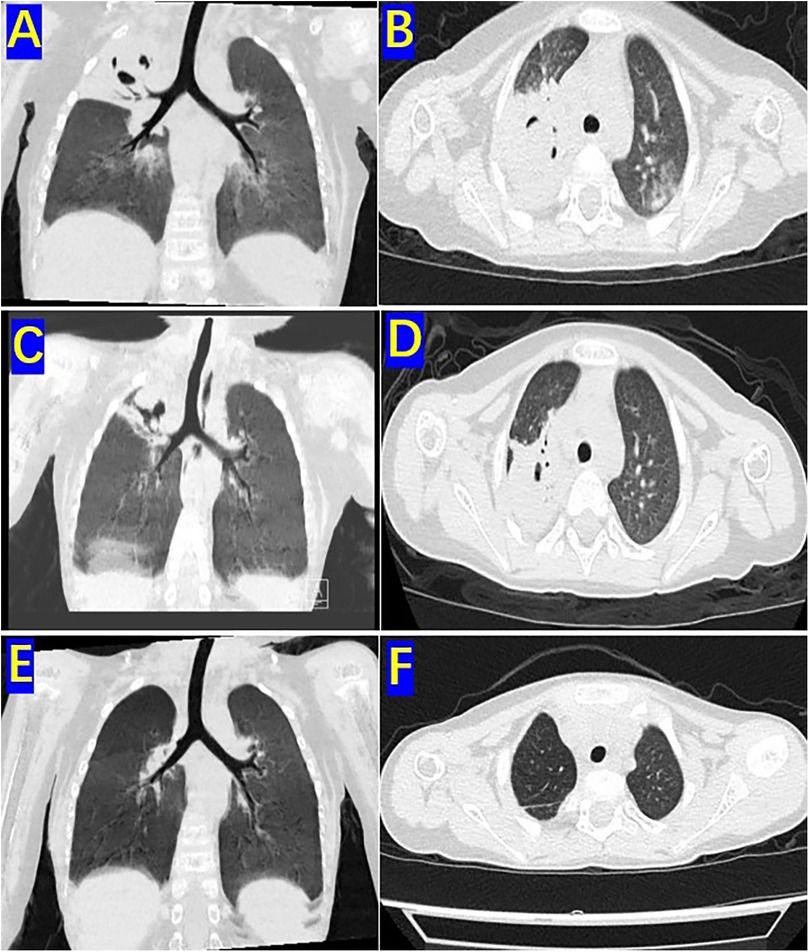

The patient was a 3-year-old boy who was diagnosed with ALL in the Department of Hematology and Oncology at our hospital one year ago. Following prednisone induction therapy, he underwent 11 cycles of chemotherapy in the same department. Two months prior to surgery, following the 11th cycle of chemotherapy, the child developed symptoms indicative of a respiratory infection, including fever, cough, and expectoration. A chest CT scan revealed extensive inflammatory lesions in the right lung, with partial consolidation predominantly in the upper lobe of the right lung (Pre-bronchoscopy treatment CT, Figures 2A,B). Initially, bacterial infection was suspected, and treatment commenced with cefoperazone-sulbactam sodium. Due to poor therapeutic response, the regimen was switched to linezolid for anti-inflammatory treatment. Subsequently, further investigations, including high-throughput gene sequencing for pathogenic microorganisms in whole blood and sputum, were performed. The patient received antifungal therapy with amphotericin B combined with oral posaconazole 1 month and 20 days prior to surgery due to infection with Rhizopus. Despite two weeks of treatment, the child continued to exhibit respiratory symptoms, including intermittent fever, cough, and expectoration. Consequently, the first FB and bronchoalveolar lavage were performed, followed by treatment with L-AmB combined with oral posaconazole. After adjusting the antifungal regimen for 2 weeks, the child's body temperature was effectively controlled. However, 20 days before surgery, the child developed hemoptysis characterized by bloody sputum, prompting a second FB and bronchoalveolar lavage. Under bronchoscopy, a fungal mass caused by Mucormycosis albuginea was observed, with complete obstruction of the anterior segment of the right upper lobe (Figure 1). Inhalation of amphotericin B was added to the original treatment regimen. After 2 weeks of treatment, the child continued to experience intermittent hemoptysis, which had slightly worsened compared to before, leading to a transfer to thoracic surgery for further management.

Two days before the operation, a follow-up chest CT scan (preoperative CT) revealed significant improvement in the inflammation of the middle and lower lobes of the right lung compared to prior findings. However, the upper lobe of the right lung exhibited extensive consolidation with cavitary changes (Figures 2C,D). The child experienced intermittent hemoptysis that progressively worsened, indicating the need for surgical intervention. After successfully correcting severe preoperative abnormalities, including hypokalemia and anemia, the patient underwent thoracoscopic surgery.

Figure 2. Pre-bronchoscopy treatment CT, preoperative CT and One-month postoperative CT: (A) sagittal view of the high-resolution chest CT lung window before two bronchoscopic bronchoalveolar lavages. (B) Coronal view of the right upper lobe on high-resolution chest CT lung window before two bronchoscopic bronchoalveolar lavages. (C) Sagittal view of the high-resolution chest CT lung window before surgery. (D) Coronal view of the upper lobe in the high-resolution chest CT lung window before surgery. (E) Sagittal view of the high-resolution chest CT lung window 1 month after surgery. (F) Coronal view of the upper lobe in the high-resolution chest CT lung window 1 month after surgery.

One month postoperatively, a follow-up chest CT scan revealed no significant signs of infection in both lungs (Figures 2E,F). Chemotherapy for ALL was continued. The child was followed up for three years after treatment completion and remained in good health with no notable discomfort.